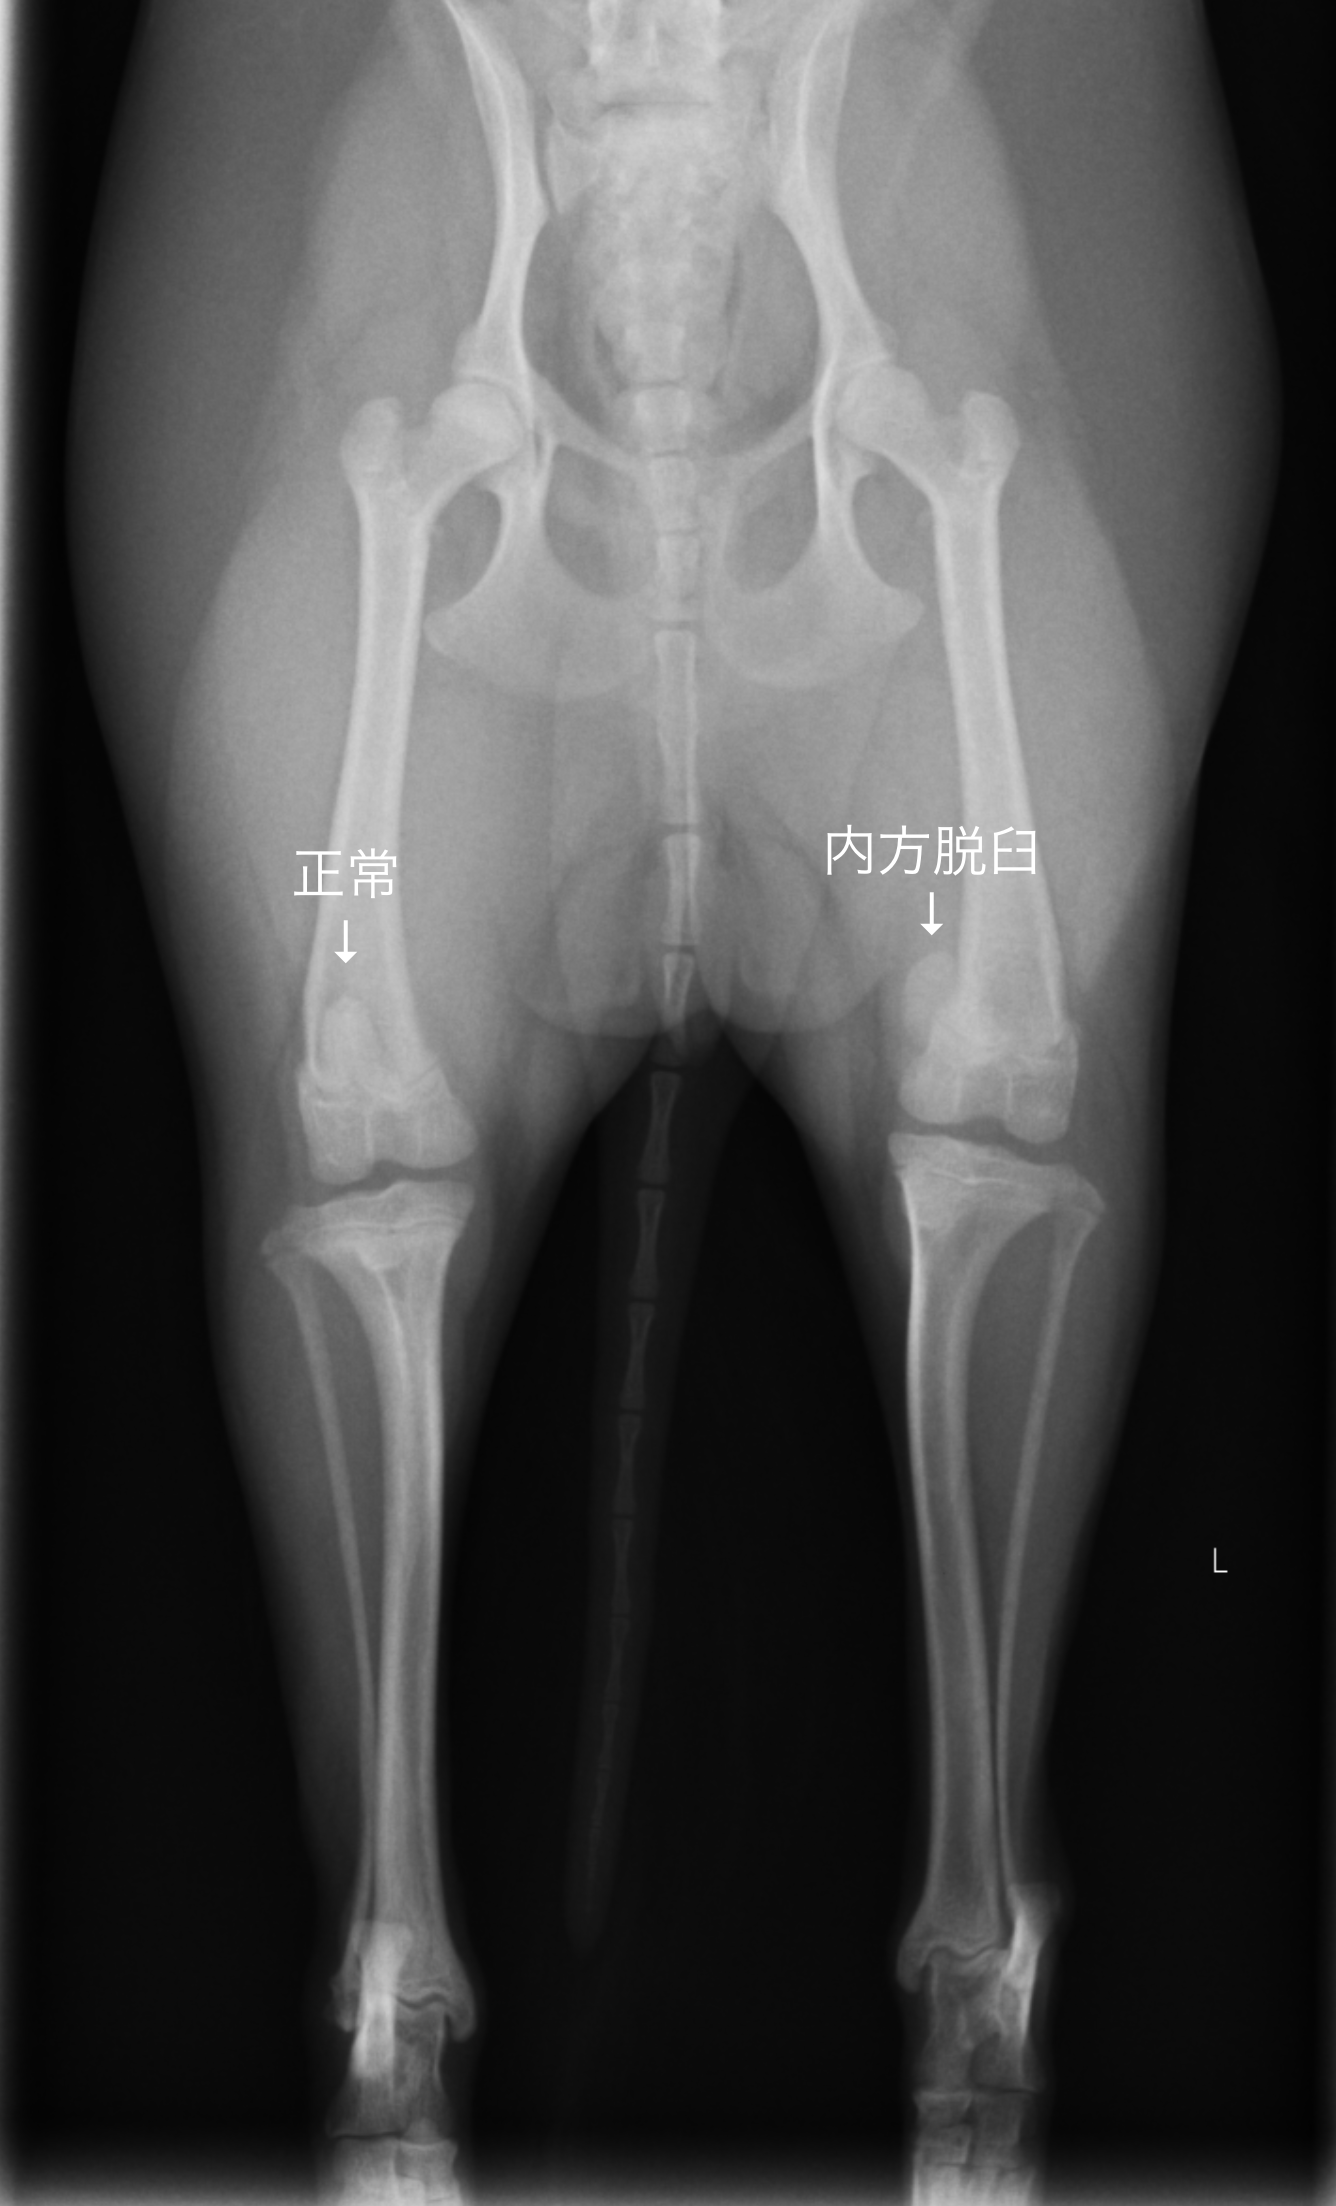

膝蓋骨脱臼(パテラの脱臼について)

●膝蓋骨脱臼について 膝蓋骨という膝のお皿が正しい位置から脱臼してしまう病気で、多くは内側にずれてしまいます。

●診断

・レントゲン検査(膝蓋骨の位置、骨の変形を見る)